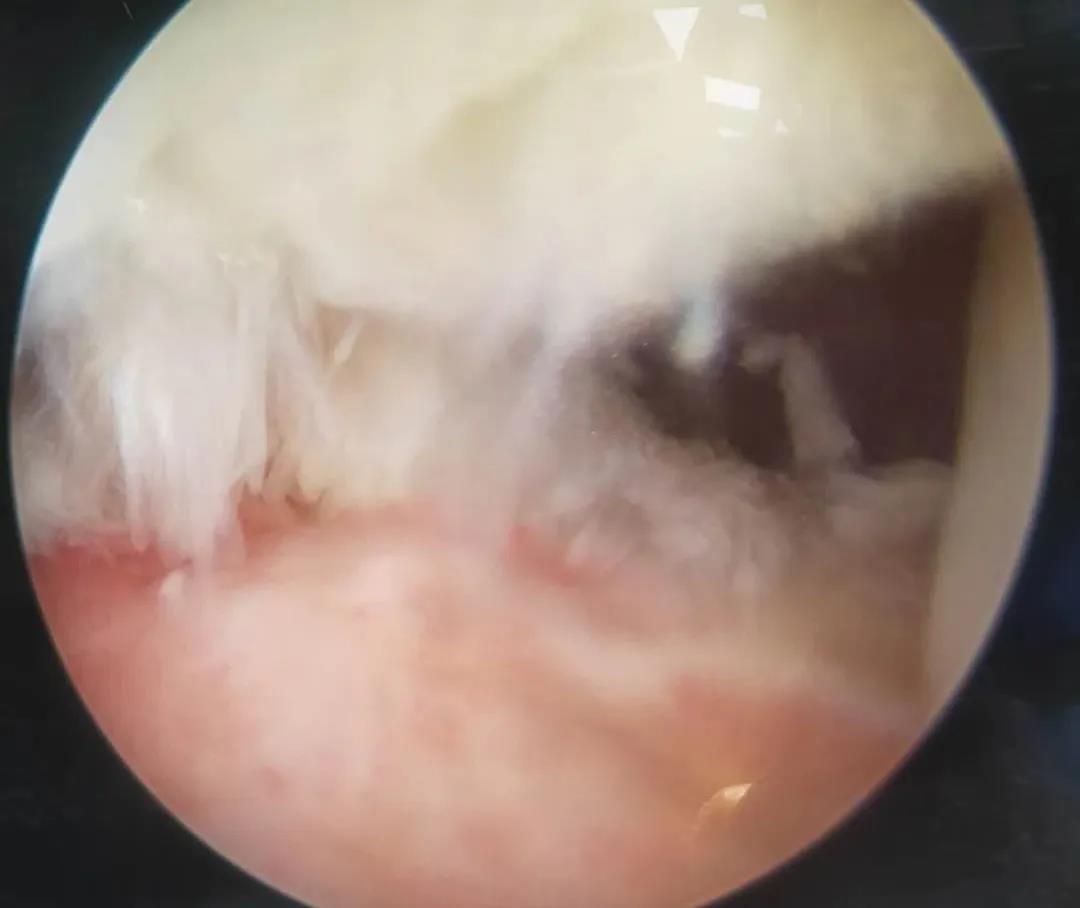

膝關節(jié)鏡

膝關節(jié)半月板損傷和前后交叉韌帶損傷是運動損傷常見疾病,半月板損傷后不能自行愈合,盡早手術可以避免繼發(fā)關節(jié)軟骨的損傷,骨二科采用關節(jié)鏡下半月板縫合手術,能少切除就少切除,能縫合盡量縫合,最大努力保留患者半月板,更好的恢復膝關節(jié)的功能。膝關節(jié)前后交叉韌帶損傷一般采用單束重建,只能恢復原來韌帶的80%的強度,骨二科采用雙束重建,能夠比原來的韌帶更粗更強,為后期的功能鍛煉及恢復提供良好的基礎。